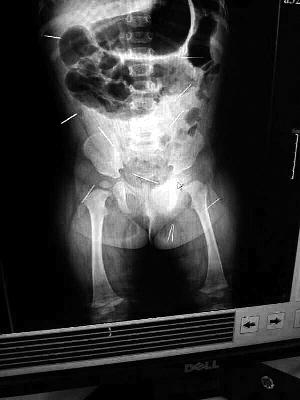

“要不是當初那幾個紅點,可能到現(xiàn)在我們還不知道孩子身體里有鋼針!”昨天,在兒童醫(yī)院住院處,萱萱爸爸范先生稱,日前原本很愛笑的萱萱突然變得有些焦躁,一抱起來就哭,孩子母親偶然間在萱萱屁股上發(fā)現(xiàn)了幾個小紅點兒,原以為是蚊蟲叮咬,就醫(yī)結果卻讓人不寒而栗。“醫(yī)院拍出的片子上,萱萱的體內有12根鋼針,插滿臀部、腹腔、骨盆等各個部位。”范先生介紹,因為鋼針已深入體內,要是孩子不哭鬧,他們很難發(fā)現(xiàn)。

北京晨報記者了解到,目前體內的12根鋼針多分布在孩子的臀部,一根在腹部,其余3根在胸腔附近,其中一根很接近心臟(如圖)。“因為孩子太小,醫(yī)生們害怕取針的時候對她造成傷害,在胸腔附近的3針可能會威脅她的生命”。